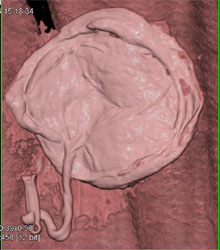

Pelvic Congestion Syndrome